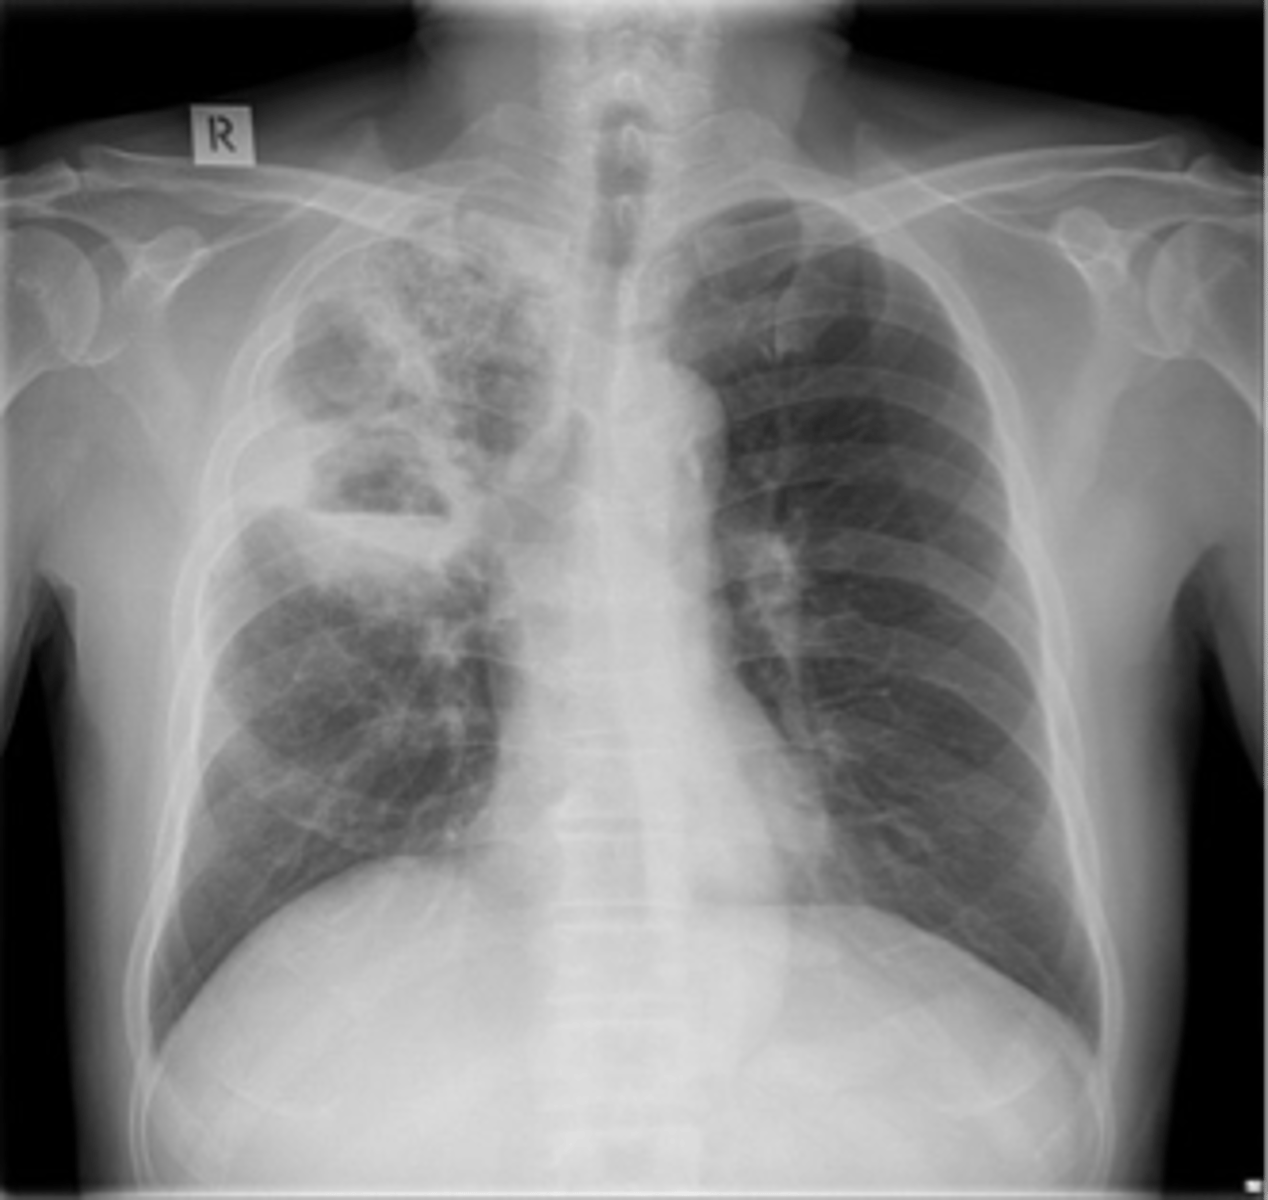

Lung cancer- squamous cell carcinoma

squamous cell carcinoma